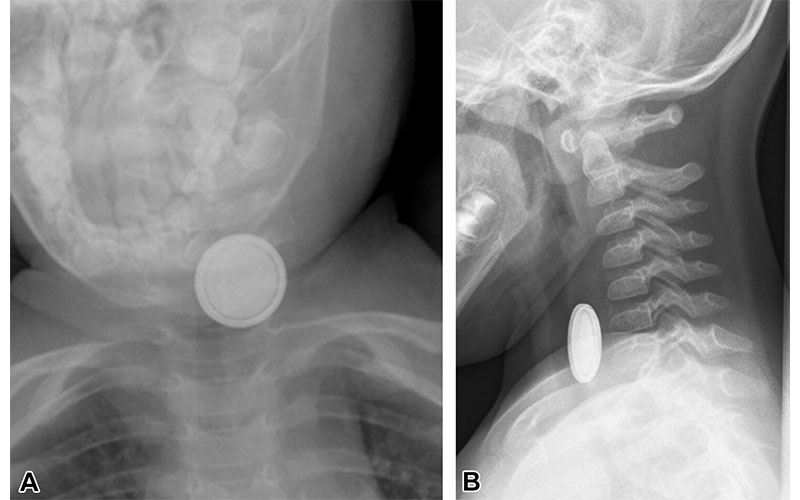

Recently ingested button battery in a pediatric patient. (A) Anteroposterior neck radiograph shows a double-ring appearance of the ingested button battery. (B) Lateral radiograph shows a beveled-edge appearance of the button battery. The location of the battery in the upper esophagus can be inferred by the round appearance of the battery in the anteroposterior projection and by the air-filled trachea observed to the right and in front of the foreign body. https://doi.org/10.1148/rg.240027 © RSNA 2024